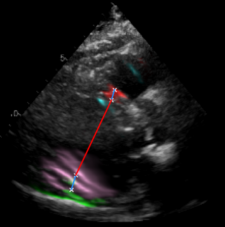

| (a) LV Measurements | (b) Label Smoothing |

Left Ventricular Hypertrophy (LVH), one of the leading predictors of adverse cardiovascular outcomes, is the condition where heart’s mass abnormally increases secondary to anatomical changes in the Left Ventricle (LV) [10]. These anatomical changes include an increase in the septal and LV wall thickness, and the enlargement of the LV chamber. More specifically, Inter-Ventricular Septal (IVS), LV Posterior Wall (LVPW) and LV Internal Diameter (LVID) are assessed to investigate LVH and the risk of heart failure [21]. As shown in Figure 1 (a), four landmarks on a parasternal long axis (PLAX) echo frame can characterize IVS, LVPW and LVID, and allow cardiac function assessment. To automate this, machine learning-based (ML) landmark detection methods have gained traction.

It is difficult for such ML models to achieve high accuracy due to the sparsity of positive training signals (four or six) pertaining to the correct pixel locations. In an attempt to address this, previous works use 2D Gaussian distributions to smooth the ground truth landmarks of the LV [9, 13, 18]. However, as shown in Figure 1 (b), for LV landmark detection where landmarks are located at the wall boundaries (as illustrated by the dashed line), we argue that an isotropic Gaussian label smoothing approach confuses the model by being agnostic to the structural information of the echo frame and penalizing the model similarly whether the predictions are perpendicular or along the LV walls.